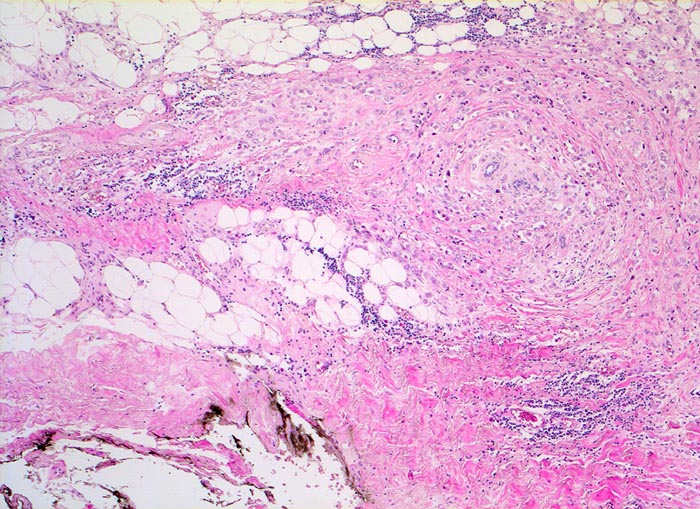

Invasiv lobuläre Karzinome sind in bis zu 80% mit einem lobulären in situ Karzinom und in 36% der Fälle mit einem duktalen Karzinom (in situ oder invasiv) assoziiert. Ein Viertel der Tumoren wächst multizentrisch. Das klassische invasive lobuläre Karzinom besteht aus kleinzelligen monomorphen Infiltraten, welche anstelle von Drüsen einreihige Tumorzellstränge bilden. Diese wachsen zirkulär um vorbestehende Drüsenläppchen (> 4221)und durchsetzen den Drüsenkörper diffus. Oft lassen sich intrazelluläre muzinhaltige Zytoplasmavakuolen nachweisen, die wie Siegelringzellen (> 4224) imponieren. Die Tumorzellen induzieren eine ausgeprägte desmoplastische Bindegewebsvermehrung.

• Multifokale Infiltrate eines invasiv lobulären Mammakarzinoms: Kleine monomorphe, zytoplasmaarme Tumorzellen bilden einreihige Ketten (gänsemarschartig = Indian files) oder sind konzentrisch um nicht neoplastische Drüsen angeordnet.

• Das Karzinom bildet keine Drüsen.

• Zytologisch blande Tumorzellen mit kleinen runden hellen Kernen.

• Reichlich dichtes desmoplastisches Tumorstroma.

• Lobuläre Neoplasie (=nicht invasiver intralobulärer Karzinomanteil): Neben den zystisch erweiterten Drüsen finden sich Mammaläppchen, deren Azini teilweise leicht vergrössert sind durch Ansammlungen von atypischen Zellen mit vergrösserten Kernen und prominenten Nukleolen. Die Basalmembran der tumorbefallen Azini ist erhalten.